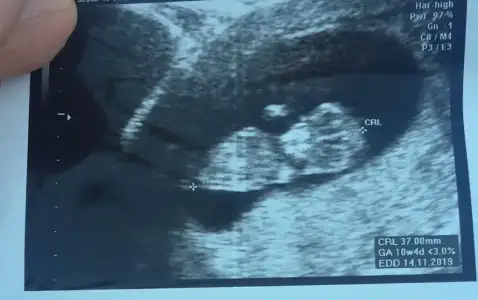

11-12-13. Haftalarda ultrason görüntüsünde bebeğin poposuna paralel yada dik bi çıkıntı oluyor bacak arasına doğru..Paralelse kız,dikse erkek oluyor cinsiyeti

Burda bişi goremiyorum teyzesi

Eklentiler

• 8C1B48F2-AA27-4182-9D6A-68843ACCD65F.webp

8C1B48F2-AA27-4182-9D6A-68843ACCD65F.webp

27,3 KB · Görüntüleme: 45